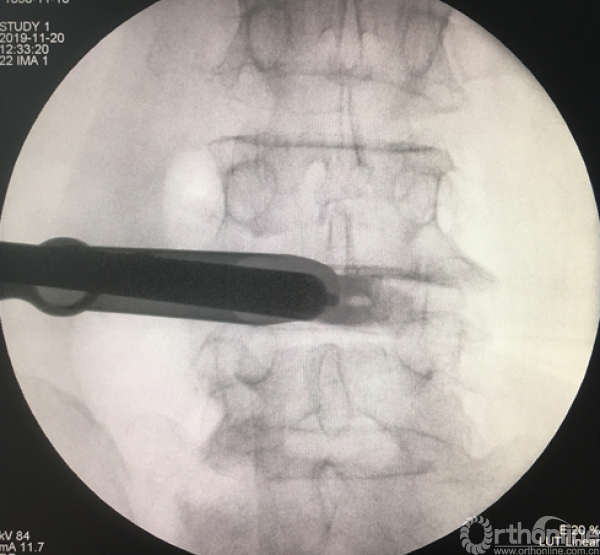

消毒前,给予椎间隙定位

放入工作套管

正侧位透视确定责任节段